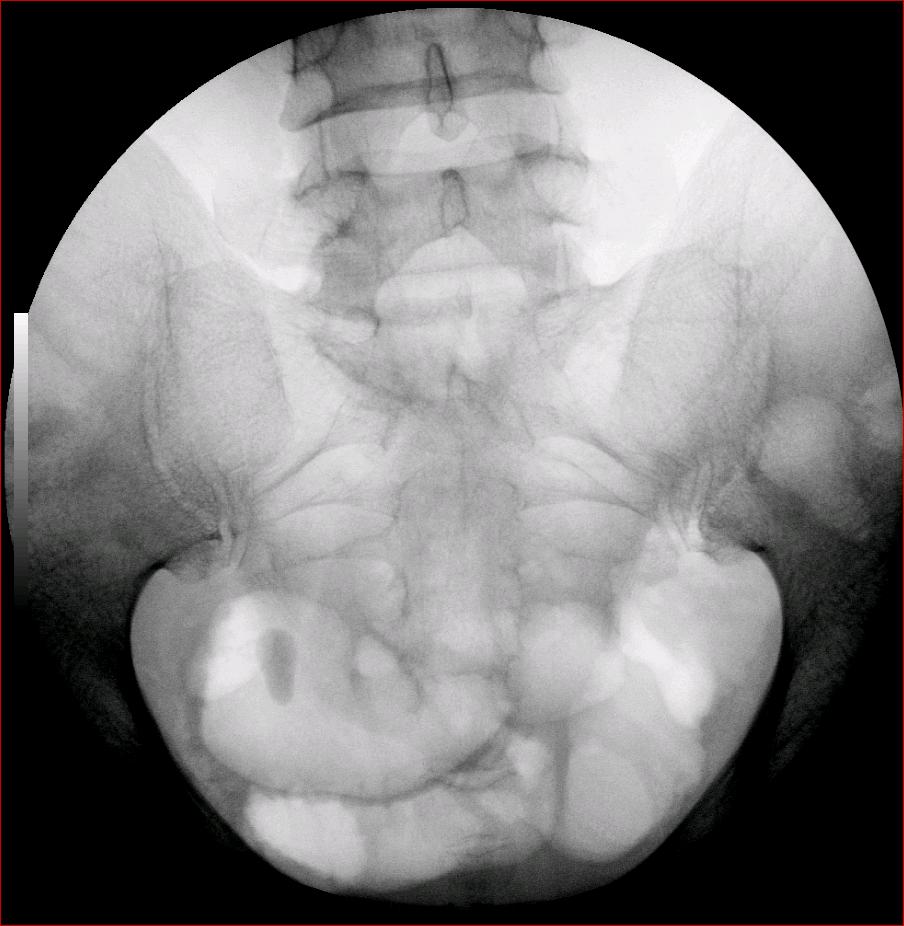

以下是引用luoxinjun在2008-2-18 15:54:00的发言:[br]右肾积水,右输尿管下端结石

以下是引用zhangxiangjun在2008-2-18 21:01:00的发言:[br]右输尿管盆段末端结石,继发其近端输尿管、右肾积水。

以下是引用hexue在2008-2-18 17:33:00的发言:[br]右输尿管下段结石并右肾及右输尿管积水扩张

以下是引用杀毒软件在2008-2-18 16:24:00的发言:[br]右输尿管下段结石,肾盂积水。